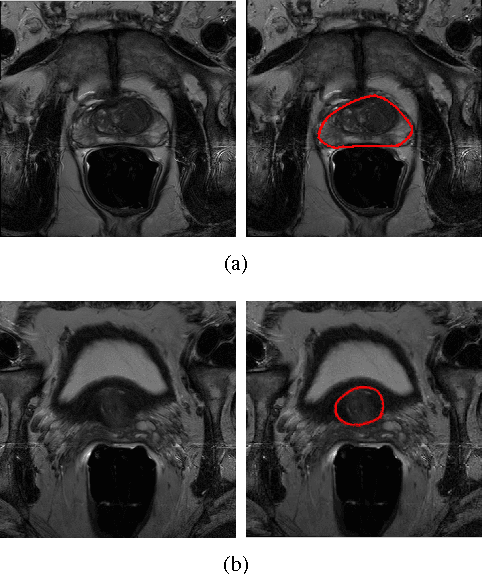

Prostate segmentation from Magnetic Resonance (MR) images plays an important role in image guided interven- tion. However, the lack of clear boundary specifically at the apex and base, and huge variation of shape and texture between the images from different patients make the task very challenging. To overcome these problems, in this paper, we propose a deeply supervised convolutional neural network (CNN) utilizing the convolutional information to accurately segment the prostate from MR images. The proposed model can effectively detect the prostate region with additional deeply supervised layers compared with other approaches. Since some information will be abandoned after convolution, it is necessary to pass the features extracted from early stages to later stages. The experimental results show that significant segmentation accuracy improvement has been achieved by our proposed method compared to other reported approaches.